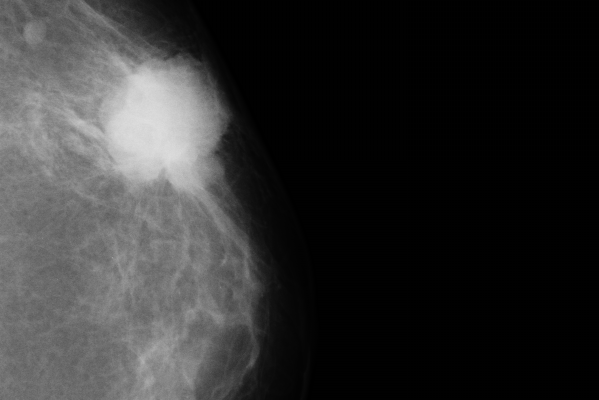

Эффективность маммографии в снижении смертности от рака молочной железы: правда или миф? В современном мире здравоохранения диагностика рака молочной железы